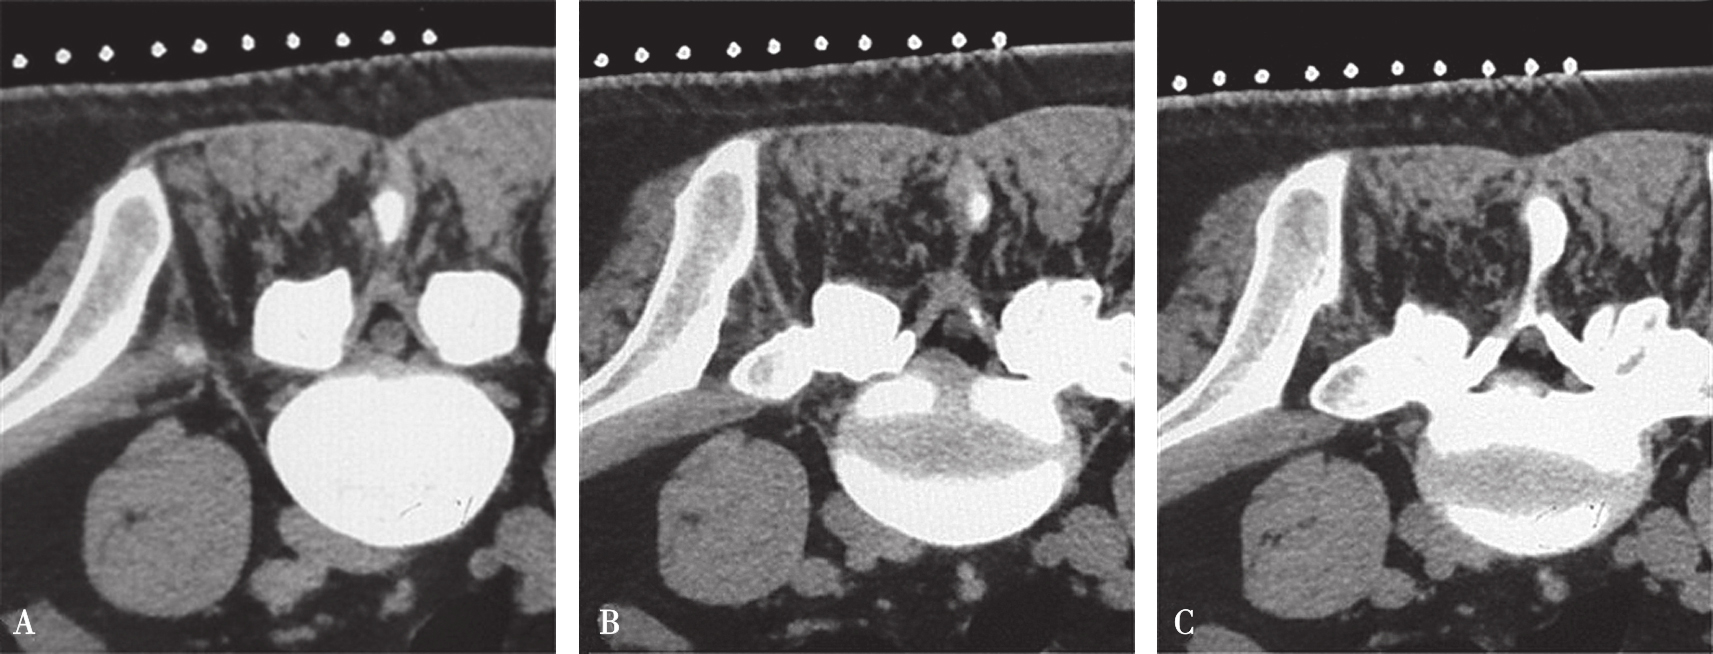

图3-3-14 沿椎弓根轴线扫描的不同层

A.椎弓根偏头侧平面;B.椎弓根中间平面;C.椎弓根偏足侧平面

在扫描产生的多层横断面中选择出最符合穿刺要求的一层,作为设计入路和引导穿刺定位的操作平面,我们将该层称为“靶点操作平面”。根据不同的手术目的选择该平面的要求也不同:避骨入路类手术如经椎板间入路椎间盘靶点定位类,应选择具有最大程度避开神经、血管、脏器、骨质而到达靶点的平面,如图3-3-12中显而易见图B是最合适的平面;经椎间隙侧方入路时的扫描图像中(图3-3-13),图B最合适;而经骨入路类手术如经皮椎体骨折复位外固定、椎体成形术等,应选择椎弓根宽大处的平面,如图3-3-14中图B作为操作平面最合适。CT机架角度扫描的横断位平面自然也是倾斜的,而穿刺定位入路是在该平面内的,因此存在如下关系:CT机架扫描角度=靶点操作平面角度=定位针穿刺时的头足倾斜角度(图3-3-15)。